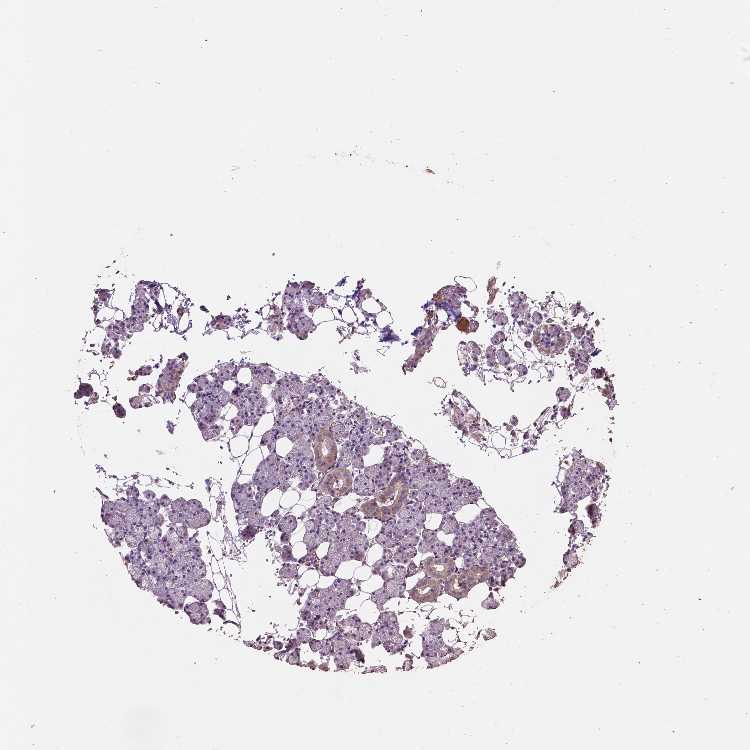

Antibody HPA066957

Glandular cells Low